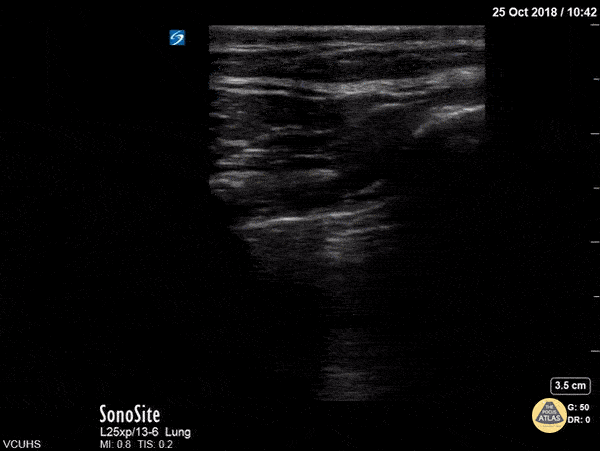

Lung point on a large pneumothorax. Dr. Stenberg

https://www.thepocusatlas.com/lung